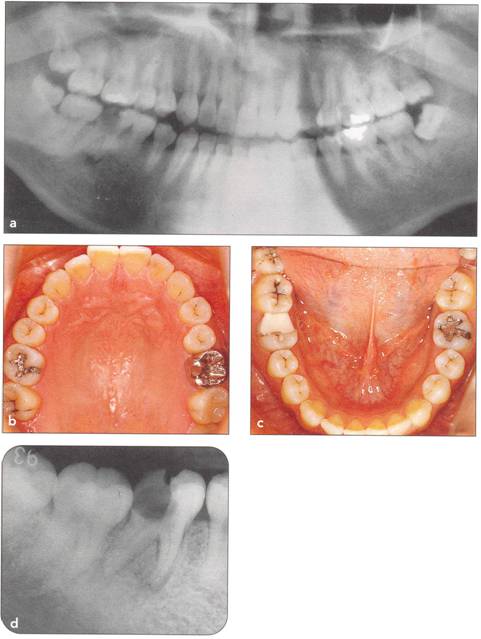

Fi 545e45f g 5-4a Pretreatment panoramic view. Mandibular left third molar will be transplanted to the area of the non restorable mandibular left second molar in a 39-yearold male. |

Fi 545e45f gs 5-4b and 5-4c Preoperative view. |

Fi 545e45f gs 5-4d and 5-4e Preoperative view of the recipient site and the donor tooth. |

Fi 545e45f g 5-4f Extracted second molar, which will be discarded. Fi 545e45f g Extracted donor tooth. The amount of periodontalligament is adequate. Transplantation was performed 6 weeks after extraction of the tooth from the recipient site. Fi 545e45f g 5-4h View of the donor site and preparation of the recipient site. |

Fi 545e45f g 5-4i After the gingival flap has been sutured and the donor tooth has been splinted. The distal aspect of the donor tooth is closed as tightly as possible. Fi 545e45f g 5-4j After transplantation. Fi 545e45f g 5-4k Two weeks after trans plantation |

Fi 545e45f g 5-41 Six weeks after transplantation. The root canals have been cleaned, shaped, and filled with calcium hydroxide. Fi 545e45f g 5-4m Three months after transplantation. The radiograph was taken after removing the splint. Fi 545e45f g 5-4n Seven months after transplantation. |

Fi 545e45f g 5-40 Seven months after transplantation. Mesial migration of the donor tooth and regeneration of alveolar bone can be observed. Fi 545e45f g 5-4p One year after transplantation. Fi 545e45f g 5-4q Two years after transplantation. |

Fi 545e45f gs 5-4r to 5-4t One year 6 months after transplantation. The donor tooth is restored with composite resin. |

Fi 545e45f g 5-4u Three years after transplantation. |